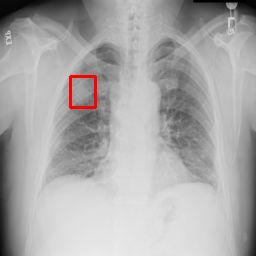

Deployments of artificial intelligence in medical diagnostics mandate not just accuracy and efficacy but also trust, emphasizing the need for explainability in machine decisions. The recent trend in automated medical image diagnostics leans towards the deployment of Transformer-based architectures, credited to their impressive capabilities. Since the self-attention feature of transformers contributes towards identifying crucial regions during the classification process, they enhance the trustability of the methods. However, the complex intricacies of these attention mechanisms may fall short of effectively pinpointing the regions of interest directly influencing AI decisions. Our research endeavors to innovate a unique attention block that underscores the correlation between 'regions' rather than 'pixels'. To address this challenge, we introduce an innovative system grounded in prototype learning, featuring an advanced self-attention mechanism that goes beyond conventional ad-hoc visual explanation techniques by offering comprehensible visual insights. A combined quantitative and qualitative methodological approach was used to demonstrate the effectiveness of the proposed method on the large-scale NIH chest X-ray dataset. Experimental results showed that our proposed method offers a promising direction for explainability, which can lead to the development of more trustable systems, which can facilitate easier and rapid adoption of such technology into routine clinics. The code is available at www.github.com/NUBagcilab/r2r_proto.